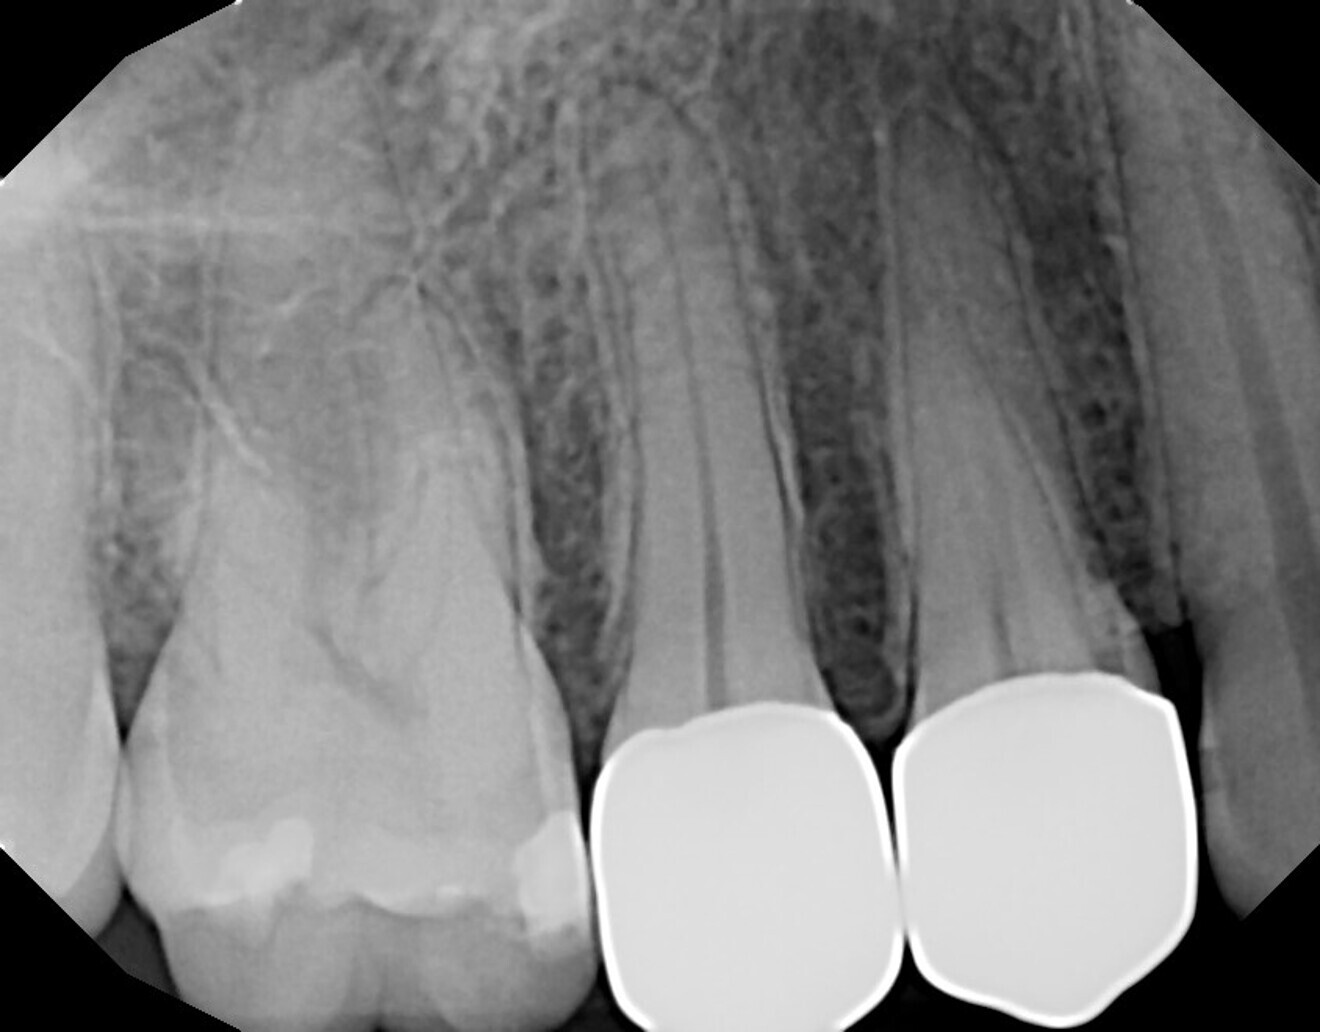

A 29-year-old female patient presented with the complaint of sensitivity in the maxillary right quadrant and requested a second opinion on the possible need for endodontic treatment that her prior dentist had recommended, owing to deep caries. She reported hot and cold sensitivity and lingering cold sensitivity of the second premolar. A periapical radiograph was taken, and it showed caries in teeth #15 and 14 on the mesio-occlusal aspect and in close proximity to the pulp in tooth #15, but no periapical pathology was noted (Fig. 18). The patient was informed of the possibility of the need for endodontic treatment and that this would be determined when the caries was removed and if a pulpal exposure was noted. Should a pulpal exposure not present, laser pulp capping could be performed and the tooth restored, but presentation of increasing tooth sensitivity at a later date would indicate that endodontic treatment may be required. The patient agreed to proceed with treatment.

The patient was seen at routine prophylactic recall appointments and continued to report an absence of sensitivity in the maxillary right quadrant. A periapical radiograph at five years after treatment demonstrated an absence of periapical pathology (Fig. 19).

Fig. 18: Initial periapical radiograph demonstrating caries on the mesio-occlusal aspect of teeth #15 and 14 and an absence of periapical pathology.

Fig. 19: Periapical radiograph at five years after laser pulp capping and restoration of tooth #15, demonstrating an absence of periapical pathology.